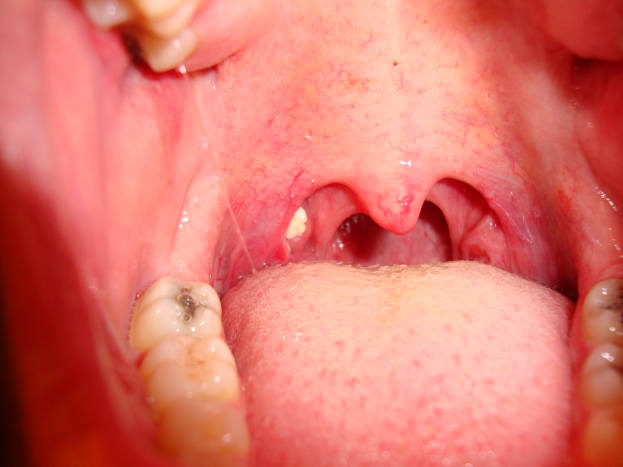

A tonsillectomy results in the formation of thick yellow white scabs.

How long do scabs take to fall off after tonsillectomy. One scab feels like its stuck in my throat feels like glass. These scabs are not signs of an infection. All three had their scabs fall off exactly 7 days after the surgery.

This is an entirely normal process and may cause a small amount of bleeding. They typically fall off between 5 and 10 days after surgery. Tonsillectomy scabs fall off around day 7 or 8.

Between 5 and 10 days after a tonsillectomy your scabs will begin to fall off. The scabs usually start falling out in small pieces. The scabs can sometimes fall off without warning and are.